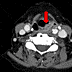

Axial neck CT (10 days after FDG-PET) shows a contrast-enhancing supraglottic mass (red arrow) extending from almost the whole of the left aryepiglottic fold down to the superior aspect of the left false vocal cord. There is likely involvement of the left posterolateral pharyngeal wall.